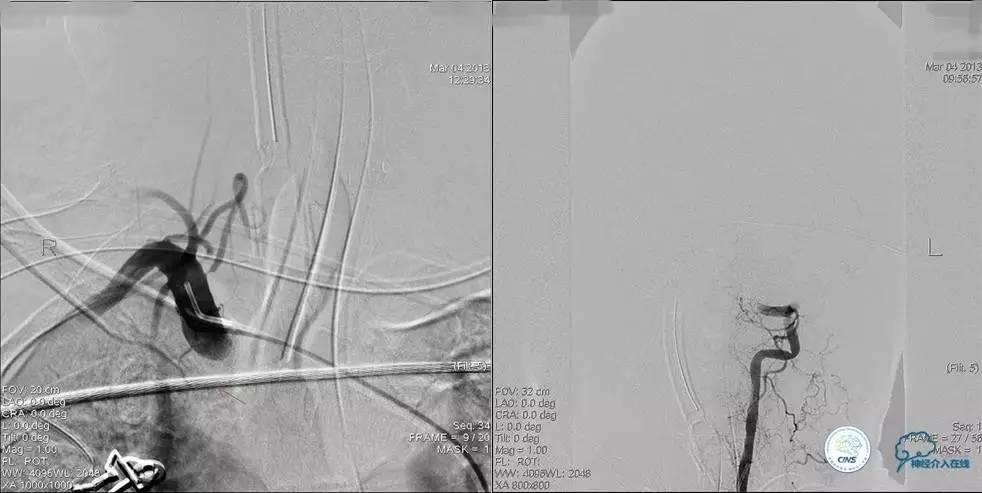

术前DSA

▼2013-12-13

▼2013-12-27

术后仍残余部分狭窄,但头晕明显缓解。

术后3个月复查时予行支架内球囊扩张,狭窄改善。